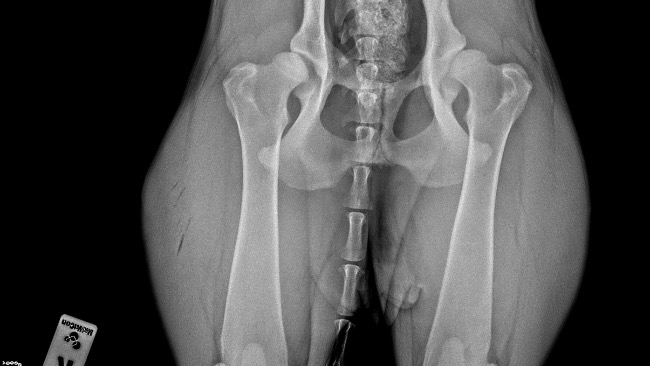

„ rzucanie” się na podłogę podczas kładzenia, dość szybko też zareagowalismy i udaliśmy się do weterynarza. Podczas wizyty wyszło że do Dysplazja genetyczna ~ tutaj oczywiście nasz błąd że nie sprawdziliśmy porządnie hodowli.

Molly regularnie uczęszczała na fizjoterapię bo lekarze dawali jej szansę „ a może jeszcze się trochę zrośnie„. Po kolejnych tygodniach/ miesiącach walki dysplazja zaczęła być widoczna gołym okiem - łopatka która „wypadała „ , wykrzywione przednie łapki - szczególnie w stawach łokciowych, jeszcze mocniejsze „rzucanie” podczas gdy pies chciał się położyć, spacery które i tak wedle zaleceń były bardzo krótkie skróciły się jeszcze bardziej, widać było że aktywnosci nawet te najprostsze sprawiały jej duży ból … oczywiście Molly cały czas przyjmowała leki i suplementację aby się tak nie męczyła..

Bardzo długo walczyliśmy sami ze sobą - po wielu konsultacjach lekarze dają jej jeszcze szansę ale do tego potrzebna jest operacja oraz późniejszą rekonwalescencja

Z góry ogromnie dziękujemy nawet za najmniejsze wpłaty oraz udostępnienia ;) zalaczam również dokumentacje medyczna